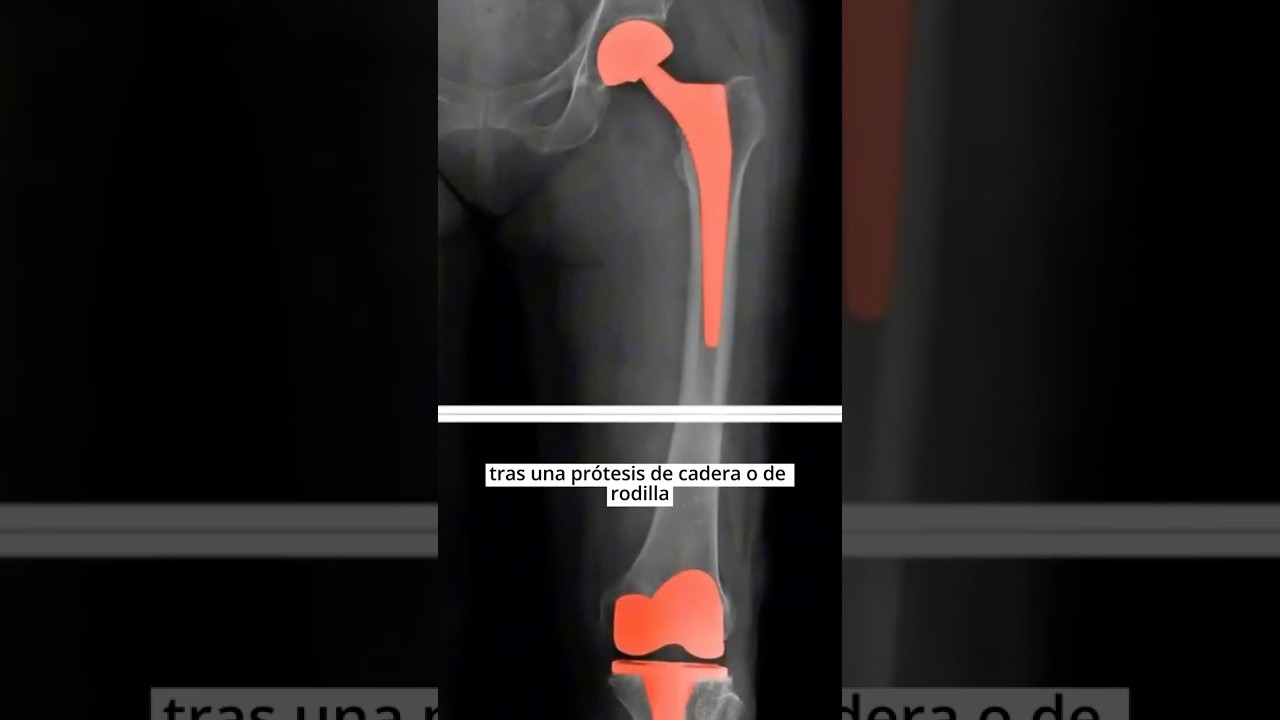

Contar con dos prótesis de cadera significa que ambas articulaciones han sido reemplazadas por componentes artificiales diseñados para restaurar la función y aliviar el dolor. Este procedimiento suele realizarse en pacientes con artrosis avanzada, fracturas o enfermedades degenerativas que afectan ambas caderas.